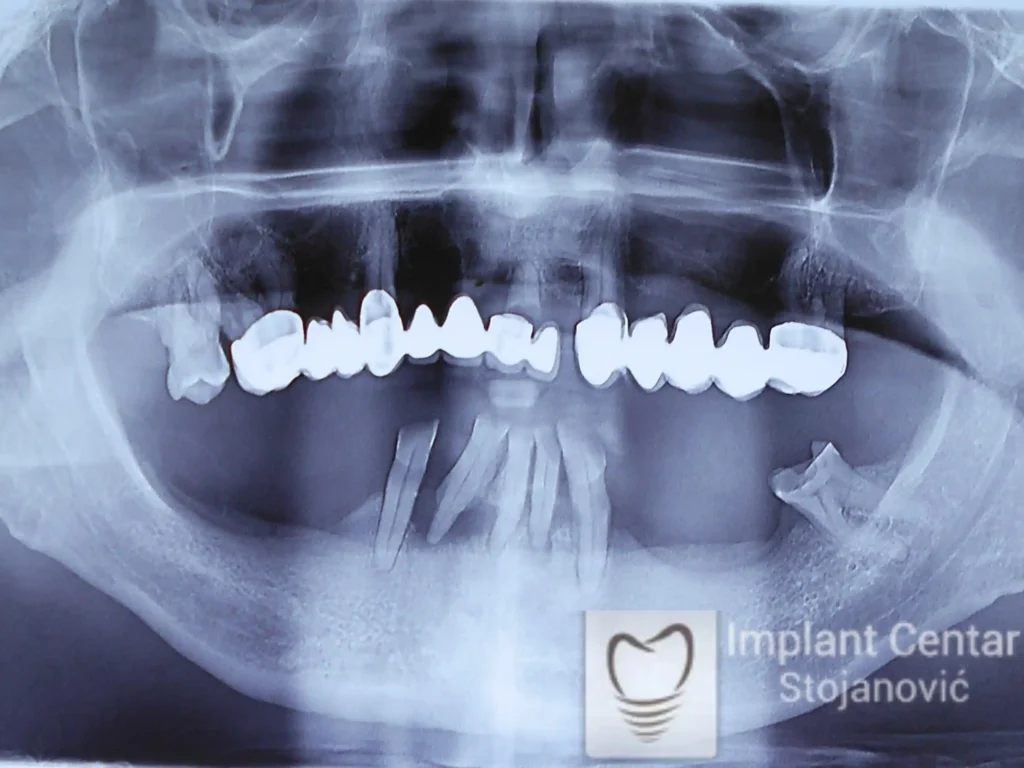

Na slici 1. i slici 2. prikazan je izgled pacijenta pre početka terapije – klinički i rendgenološki.